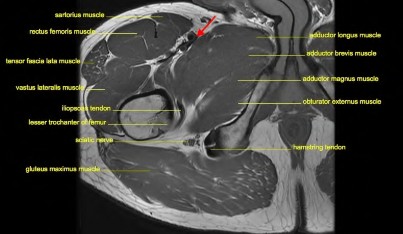

When performing a direct anterior approach to the hip for total hip arthroplasty, the internervous plane utilized is between the tensor fasciae latae (TFL) and the sartorius superficially. Which two nerves supply these muscles respectively?

Explanation

A direct anterior approach to the hip utilizes an internervous and intermuscular plane. Which of the following accurately describes this superficial interval?

A surgeon is performing a total hip arthroplasty via the direct anterior (Smith-Petersen) approach. This approach exploits the internervous plane between which two muscle groups?